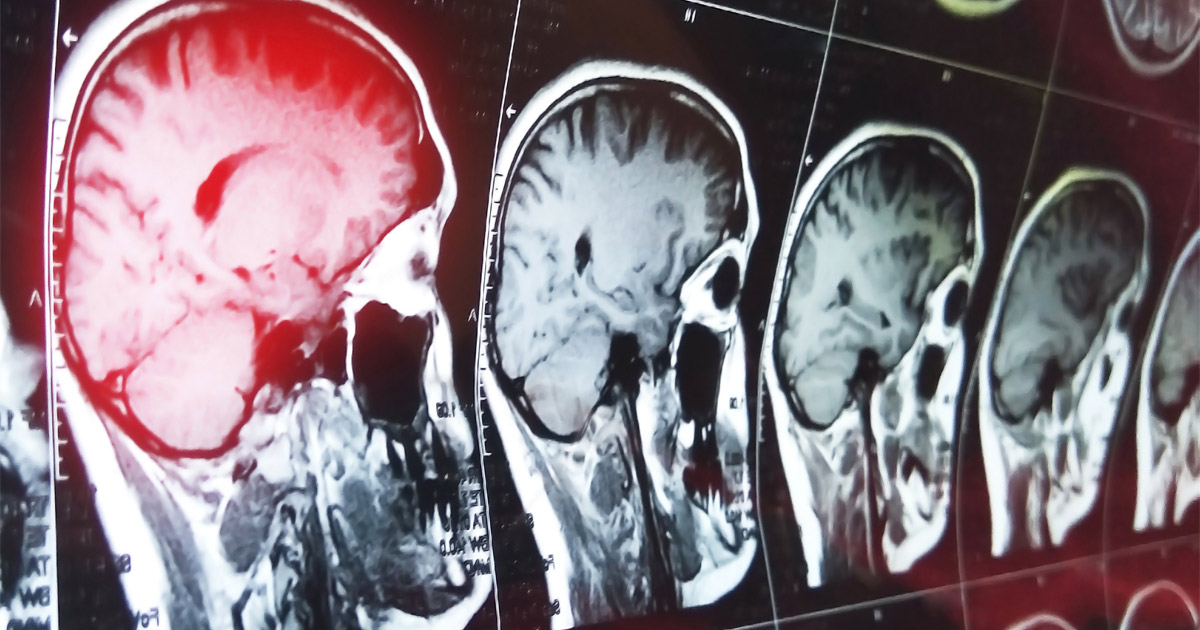

A concussion is just one of the brain injuries that you may suffer in a car accident. There is a chance that you can sustain lasting damage to your brain in the following ways:

- Diffuse axonal injury: The violent shaking in a car accident, or the impact to your head, can cause brain fibers to be sheared. Diffuse accidental injuries are a form of permanent brain damage that will change the course of your life.

- Contusions: Bruising on the brain has the potential to cause serious injury because the pooling of blood can result in the death of vital brain tissue.

- Coup-contrecoup injuries: Your brain can move back and forth in your head in a car accident. Not only can it strike the base of your skull, but it can also hit the opposite side when it rebounds.